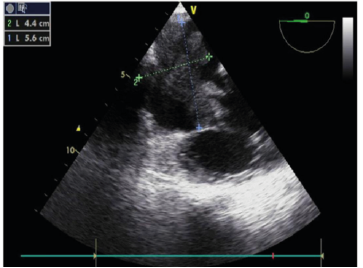

TEE A large mass was identified within the right atrium. TEE revealed a 5.6 × 4.4 cm mass with markedly irregular (malignant) borders. A portion of the mass extended into the tricuspid valve during systole, causing moderate-to-severe tricuspid regurgitation.

Figure 1: TEE revealed a 5.6 × 4.4 cm mass with markedly irregular borders